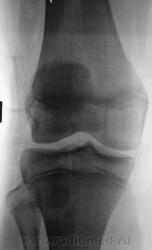

Пациент был направлен на рентгеновское исследования обоих коленных суставов по поводу болеши "Осгут-Шлаттера"

Нет, я был не прав, что утверждал, что на прямой рентгенограмме бугристость не отображается. Мы, на пленке уже вообще не работаем, оказалось, что на "цифре" на прямой отображается и ох, как хорошо.

Кроме остеохондропатии бугристостей у пациента явная латеропозизия надколенников и бугристостей большеберцовых костей, что свидетельствует о дисплазии мыщелков бедренных костей, вероятнее всего клинически проявляющаяся болями в переднем отделе коленных суставов (под надколенниками).

Интересно было бы посмотреть на аксиальные снимки надколенников. Явно ожидается уплощение медиальных мыщелков и межмыщелковых углублений бедренных костей.